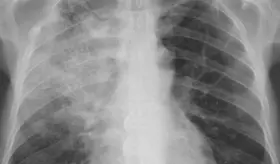

Algunos virus, pulmonía, asma y otras condiciones comparten síntomas y hasta hallazgos radiológicos, por lo que solo un especialista puede diferenciarlas con precisión.

La gripe no solo daña los pulmones, también altera su equilibrio bacteriano, pues al modificar la microbiota respiratoria, abre la puerta a infecciones graves como la neumonía.